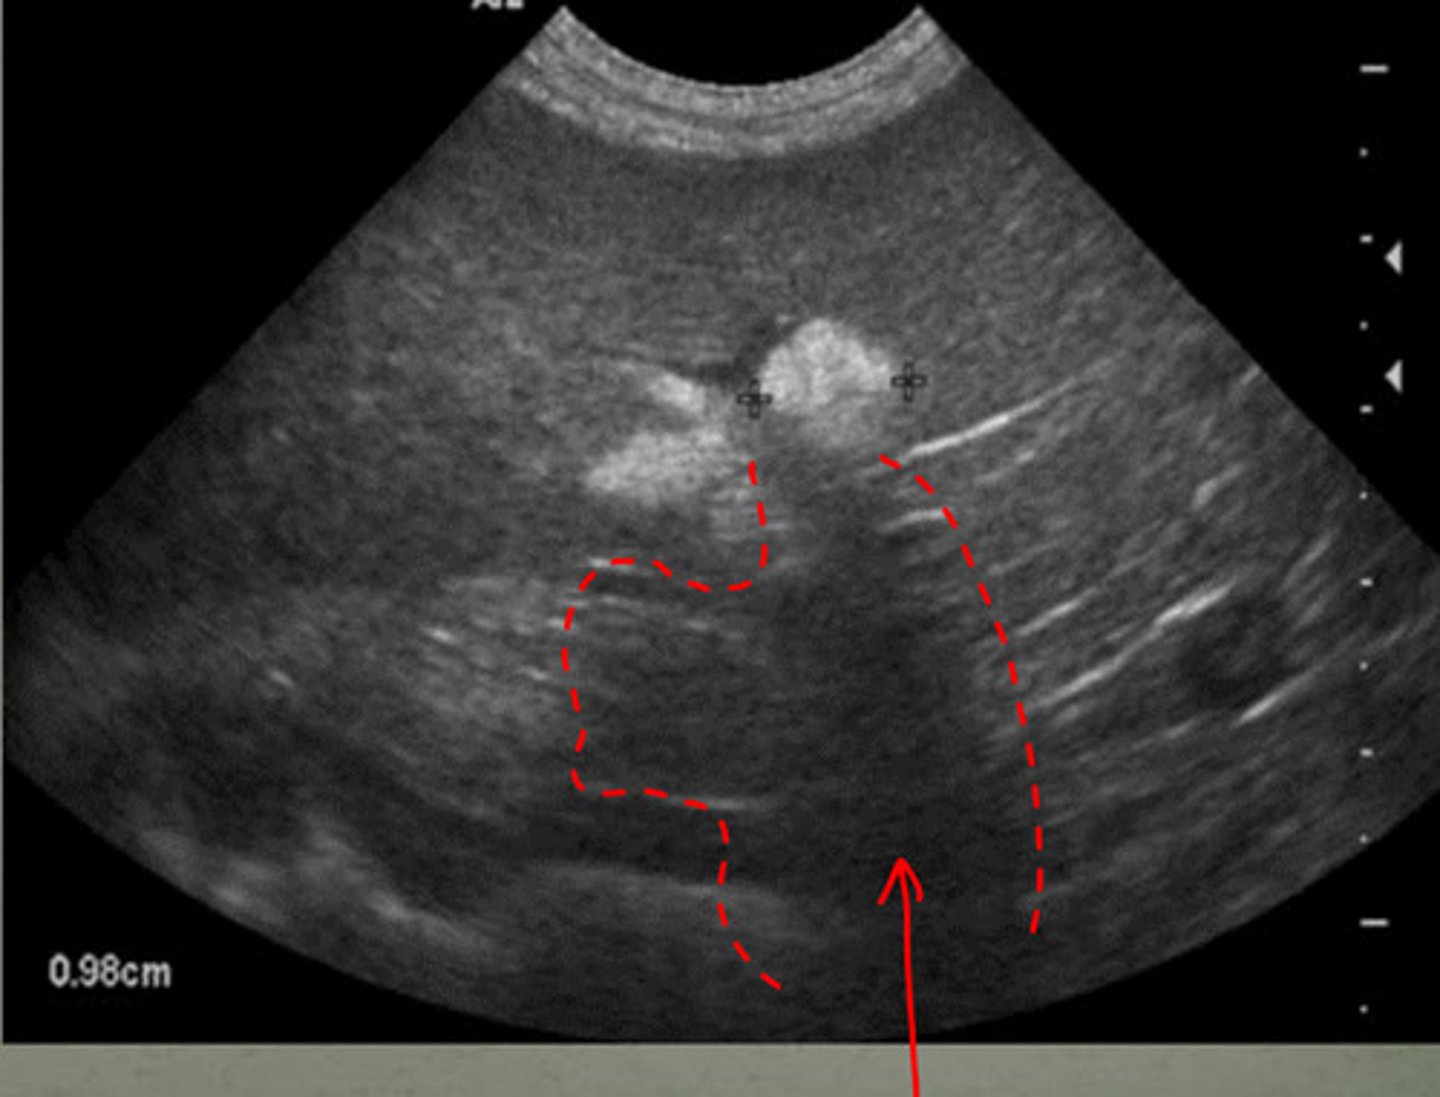

shadowing underneath the mass

if there is a hyperechoic mass in the spleen, what artifact will occur due to it?

shadowing due to the splenic mass

what are the arrows indicating? (there is a mass in this spleen)